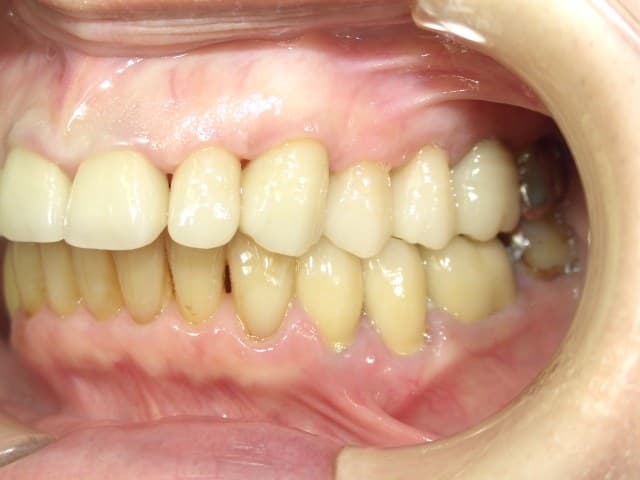

治療終了時です

歯周治療からスタートし、

「PCR(磨き残し)10%以下、BOP(歯肉からの出血)4%以内」を目標としたセルフケアトレーニング、歯周内科、LAD治療、SRPと行っていきました。

治療中は、チェアタイムも一般診療より倍以上長い為とても大変だったと思うのですが、本気で健康を手にしたいと思って頂けていたので、セルフケアも含めてとても真剣に取り組んで頂けたと感じています。